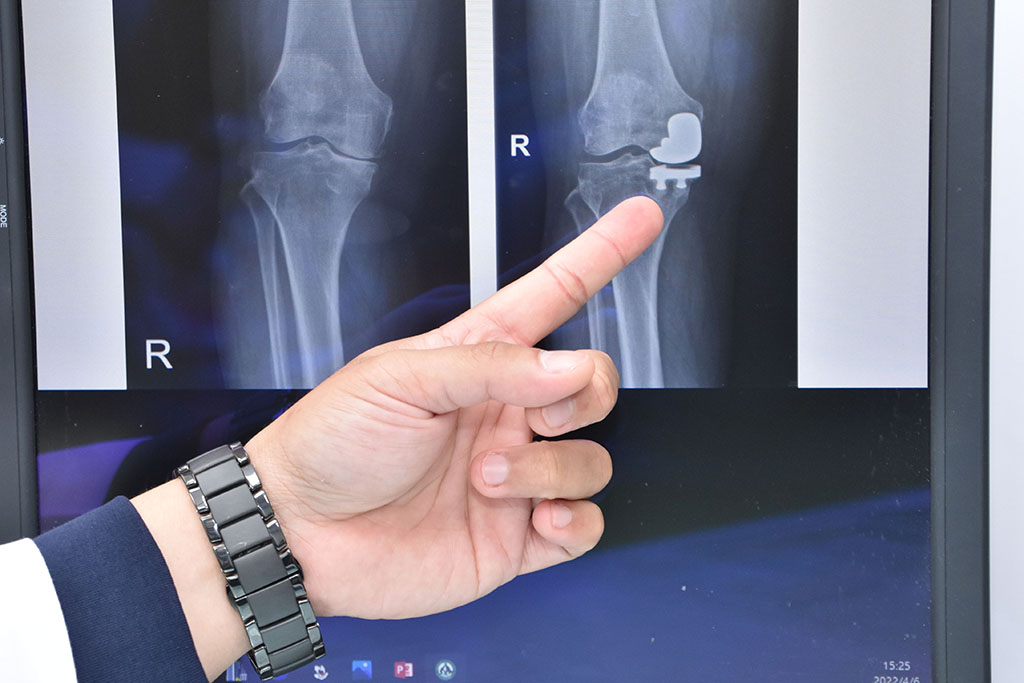

陳志鎧醫師表示,膝蓋退化並不一定要換整個膝蓋,可進行微創半套人工膝關節置換。

阿嬤內側膝關節退化,關節腔幾乎沒有空隙。

阿嬤經半套人工關節置換後,關節腔再度有了空間。